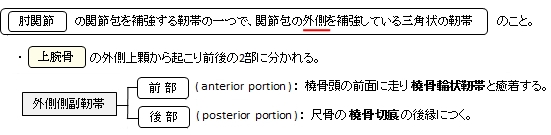

外側側副靭帯(肘関節)とは

以下が肘関節を補強する靭帯になる。

The composition of the triangular ligamentous structure on the lateral side of the elbow varies widely between individuals[1] and can be considered either a single ligament,[2] in which case multiple distal attachments are generally mentioned and the annular ligament is described separately, or as several separate ligaments,[1] in which case parts of those ligaments are often described as indistinguishable from each other.

In the latter case, the ligaments are collectively referred to as the lateral collateral ligament complex (LCLC), consisting of four ligaments:[1]

- the radial collateral ligament [proper] (RCL), from the lateral epicondyle to the annular ligament deep to the common extensor tendon[1]

- the lateral ulnar collateral ligament (LUCL), from the lateral epicondyle to the supinator crest on the ulna. Near the attachment on the humerus this ligament is normally indistinguishable from the RCL and can be considered the posterior portion of it.[1] Martin 1958 described the distal part of the LUCL as "a definite bundle which normally crosses the annular band and gains attachment to the supinator crest, frequently to a special tubercle on that crest" but didn't name it.[3]